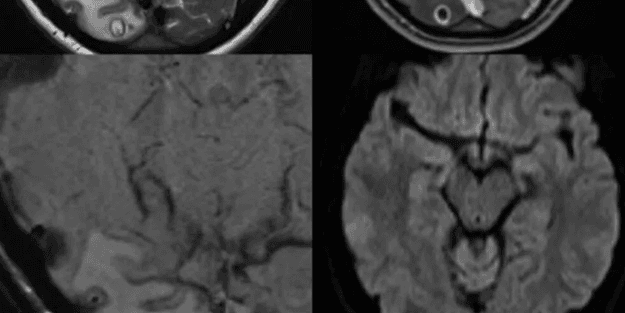

Doktorların yaptığı MR taramasının ardından kadının başının arkasındaki oksipital lobda 8 mm uzunluğunda bir lezyon bulundu.

Cerrahlar, herhangi bir komplikasyon yaşanmadan kiste benzeyen şeyi çıkarmayı başardı; ne var ki çıkardıkları parçanın insan dokusu olmadığını gördü.

DNA testi, insanlara genelde az pişmiş domuz etinin yenmesiyle bulaştığı için domuz tenyası olarak da bilinen Taenia Solium'la bir eşleşme buldu.

Geçen ay The American Journal of Tropical Medicine and Hygiene adlı bilimsel dergide yayımlanan vaka çalışmasının yazarları, "Vakanın Avustralya'da görülen ilk yerli nörosistiserkoz (merkezi sinir sisteminin tenya larvasıyla enfekte olması sonucu ortaya çıkan hastalık) vakası olduğuna inanılıyor. Avustralya'da daha önce görülen vakalarda hasta ya göçmendi, ya da endemik bölgelere gidip geri gelen sakinlerdi" ifadelerini kullandı.